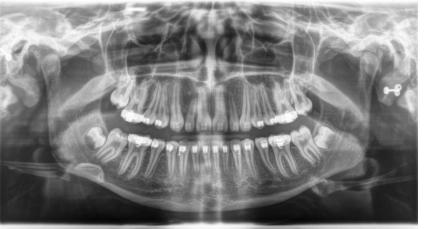

Für den Zahnarzt haben Röntgenaufnahmen einen unverzichtbaren Stellenwert in der Diagnostik und Behandlungsplanung. Für die Implantologie und viele andere zahnärztliche Bereiche bietet das digitale Röntgen eine optimale Möglichkeit der Vorplanung und Unterstützung während der Behandlung. Digitale 2D-Röntgenbilder und DVT´s/ 3D-Röntgenbilder können wir in besonders hoher digitaler Qualität und geringer Strahlendosis durchführen.

sehr hohe Auflösung und Kontrast sehr geringe Strahlenbelastung sofortige Bilddarstellung in Echtzeit optimale Vergrößerungsmöglichkeiten umfangreiche Bildnachbearbeitung punktgenaue Vermessung von Strecken gemeinsame Ergebnisauswertung mit dem Patienten Hochauflösende Panoramaaufnahme: